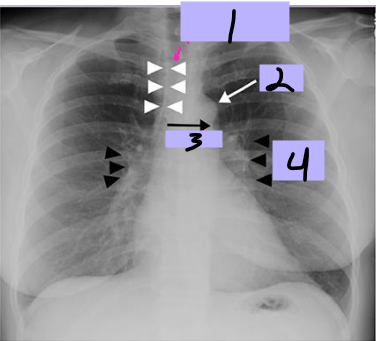

Aortic arch

#1

Superior vena cava

#2

Right pulmonary artery

#3

Right descending pulmonary artery

#4

Right atrium

#5

Right ventricle

#6

Left pulmonary artery

#7

Descending aorta

#8

Left ventricle

#9

Inferior vena cava

#10

Paratracheal stripe

#1

Aortic knob

#2

AP window

#3

Hila

#4